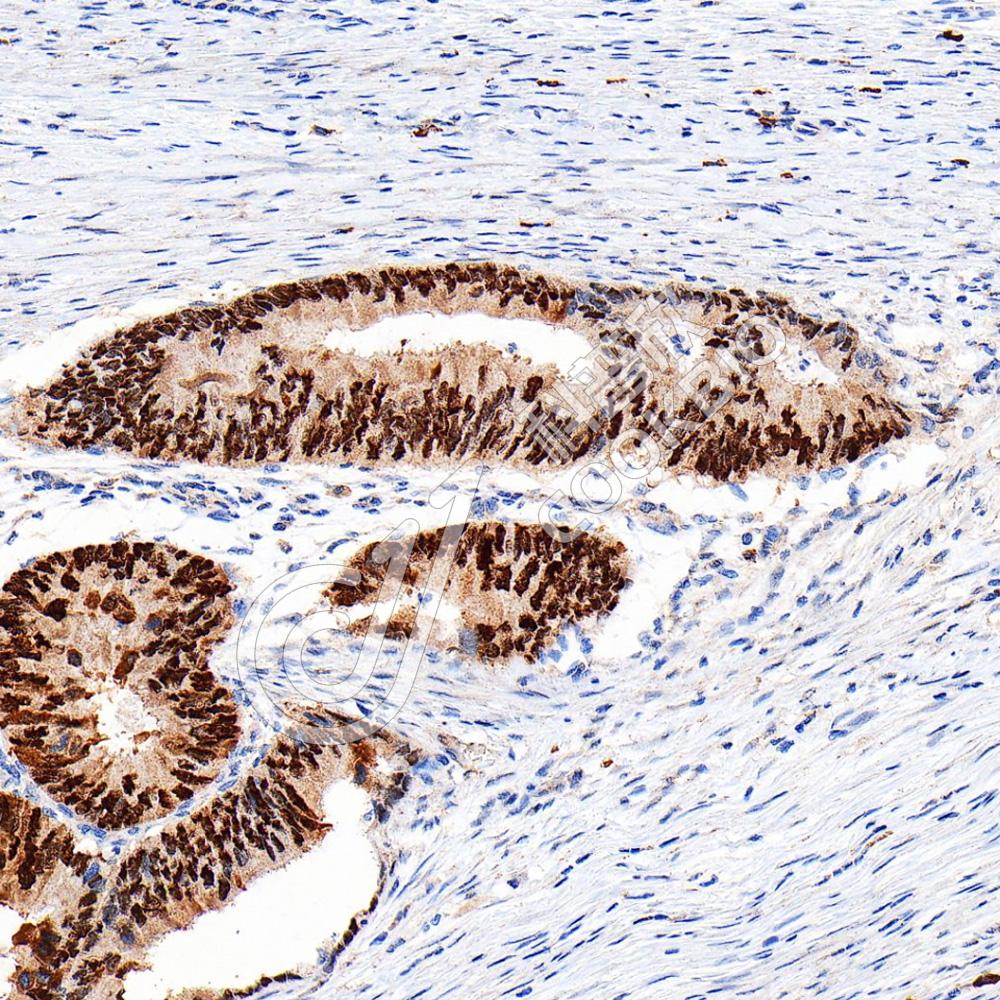

IHC检测HINT1蛋白(货号 K1336033).

样品: 人结肠癌, 4%多聚甲醛 (货号KSG1101) 固定12-24小时.

抗原修复: 柠檬酸抗原修复液(干粉, pH 6.0) (KSG1201), 98℃, 20分钟.

—抗: 1: 800稀释, 4℃ 孵育过夜.

二抗: S-vision免疫组化多聚二抗(山羊抗兔),即用型 (货号KB3906), 室温孵育20分钟.